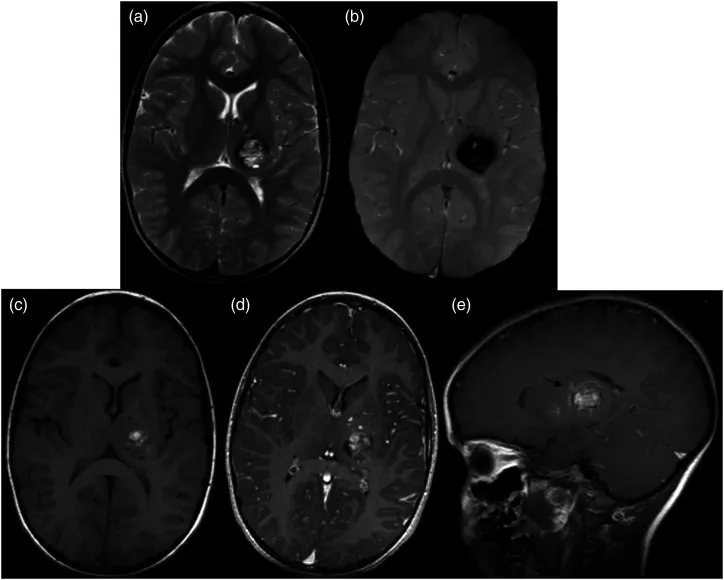

26岁男性因突然头痛、呕吐和意识恶化就医。CT扫描显示间脑后部出血性病变(图1左)。诊断为丘脑肿瘤,给予40Gy分次外束放射治疗。放疗后脑室增大,并插入脑室-腹膜分流器。放疗一年后,丘脑出血住院。再次进行MR检查,诊断修改为丘脑海绵状血管瘤(图1右)。,选择外科手术切除。

图1,左:头颅CT扫描显示初期的病变诊断为丘脑肿瘤。右:40 gy分割放疗一年后,根据磁共振成像,左丘脑病变被重新考虑为丘脑海绵状血管瘤。与未辐照的对照CH组织样本相比,治疗后病变间质存在内皮细胞损害和明显纤维化。

▼40 gy放射治疗后的丘脑海绵状血管瘤组织样本:可见明显的含铁血黄素色素沉着,提示放疗后组织新形成的毛细血管出现微出血。